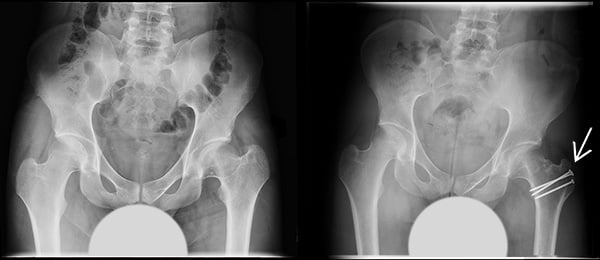

Commonly labral repair or reconstruction can be performed, impingement by the acetabulum or upper femur can be addressed. Deformities that had resulted from prior pediatric conditions such as SCFE or Perthes can be improved. Before closing the incision, the separated trochanteric bone fragment with the muscles is securely held in place with screws to maintain stability during healing. [Figure 2]

Figure 2. Anterior-to-posterior (front-to-back) X-ray images, before and after surgical dislocation of the left hip. X-ray on the right shows screw reattachment of the greater trochanter.